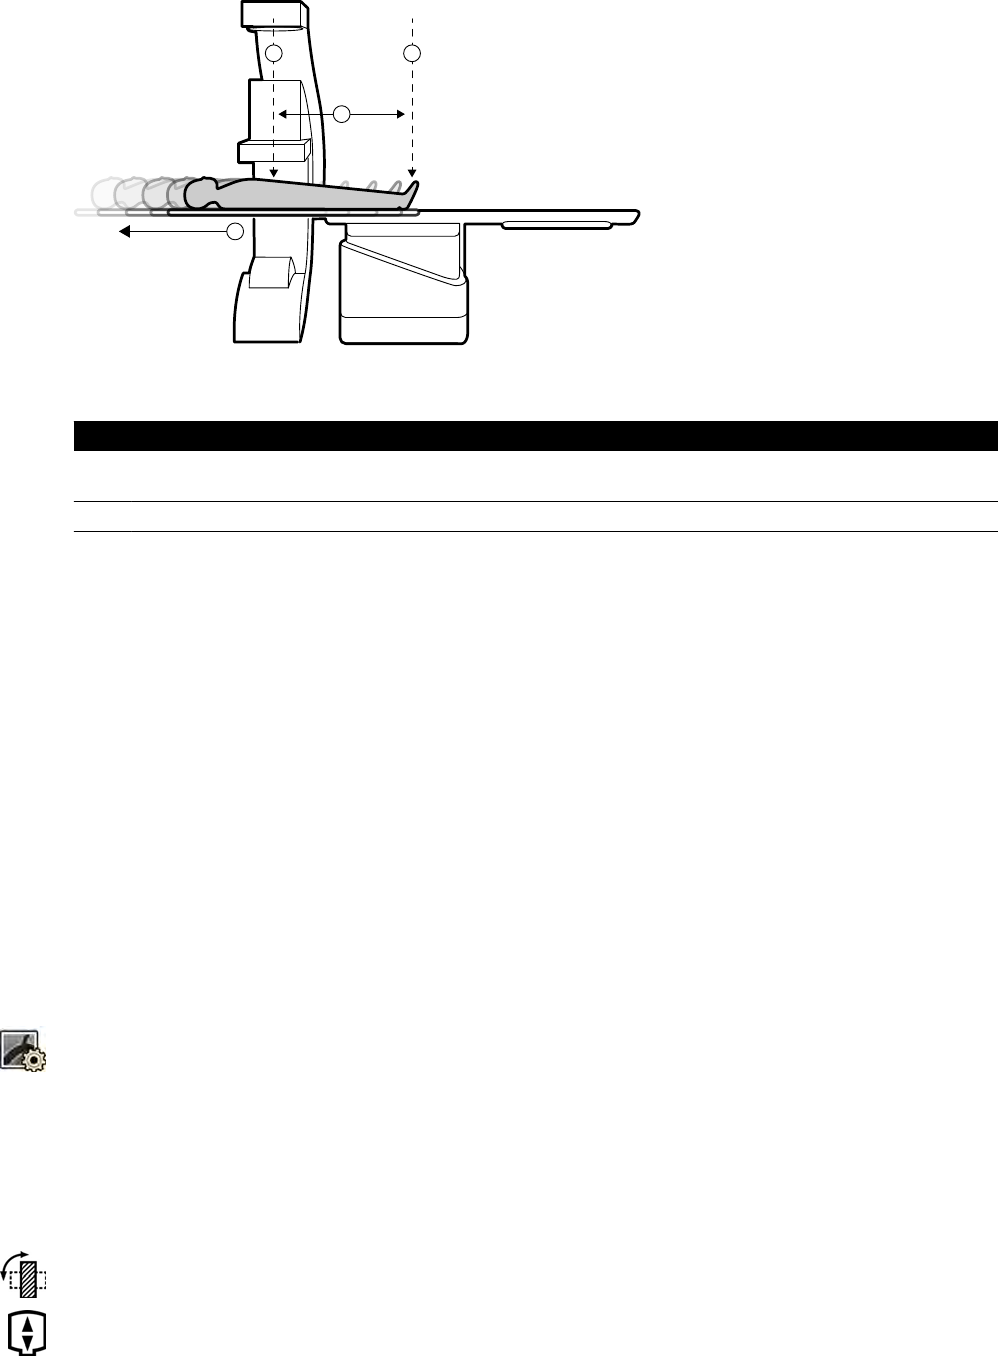

5.9.2 Ustawianie ramienia C........................................................................................... 55

5.9.3 FlexMove................................................................................................................56